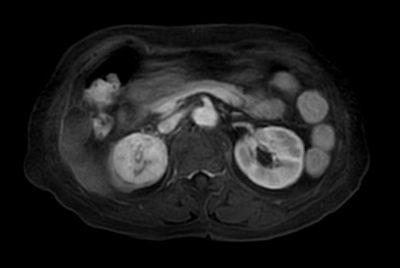

Multi-phase, contrast-enhanced renal imaging